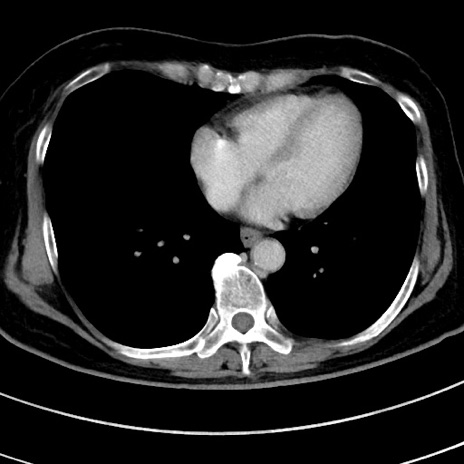

症例9(横断像)

【症例】 60歳代女性

【主訴】むかつき、みぞおちの痛み

【現病歴】3日前よりむかつきがあり、食事がとれない。

【既往歴】糖尿病

【身体所見】発熱なし、心窩部圧痛軽度あるも、腹膜刺激症状なし。

【データ】WBC 7400、CRP 1.92